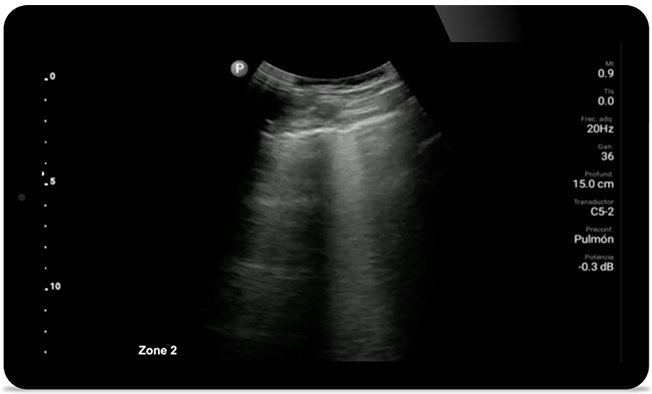

Keep an eye on COVID pneumonia

Lumify can help give results similar to a chest CT when evaluating pneumonia and adult respiratory distress syndrome.